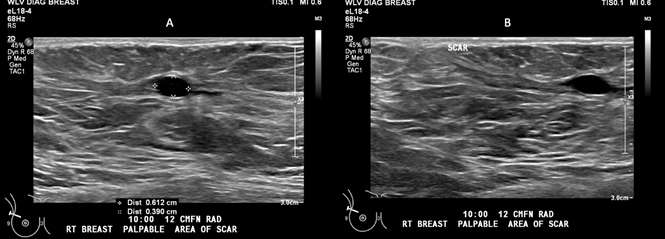

Case: Fat Necrosis of Breast Figure 1

Figure 1: 69 year old female patient with history of right breast cancer status post lumpectomy, with a newly palpable mass in the right breast. (A) Anechoic oval mass measures up to 6 mm. No posterior acoustic enhancement or shadowing is present. (B) Adjacent area of scarring related to post-surgical changes of prior lumpectomy.